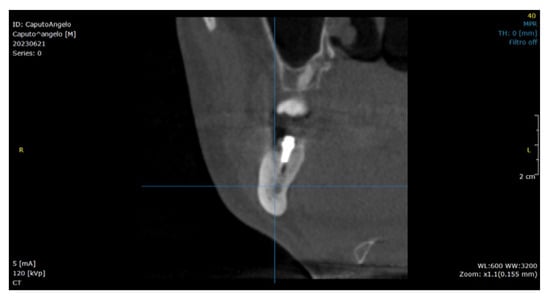

:1. Introduction

2.2. Surgical Technique